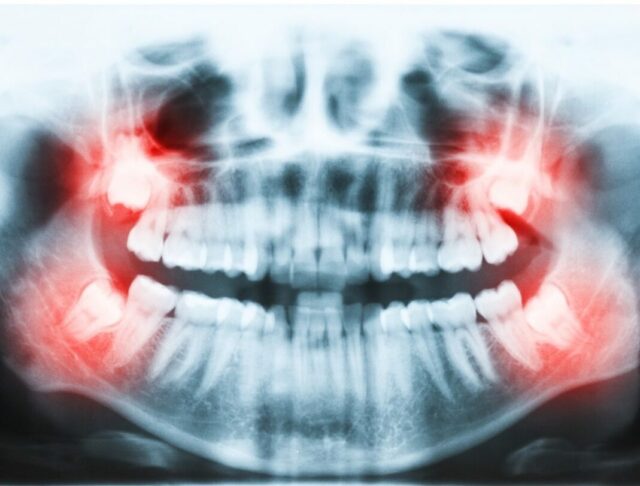

Learn more about available cosmetic and restorative procedures like dental veneers, snap-in dentures, dental implants, all on 4 dental implants and more.